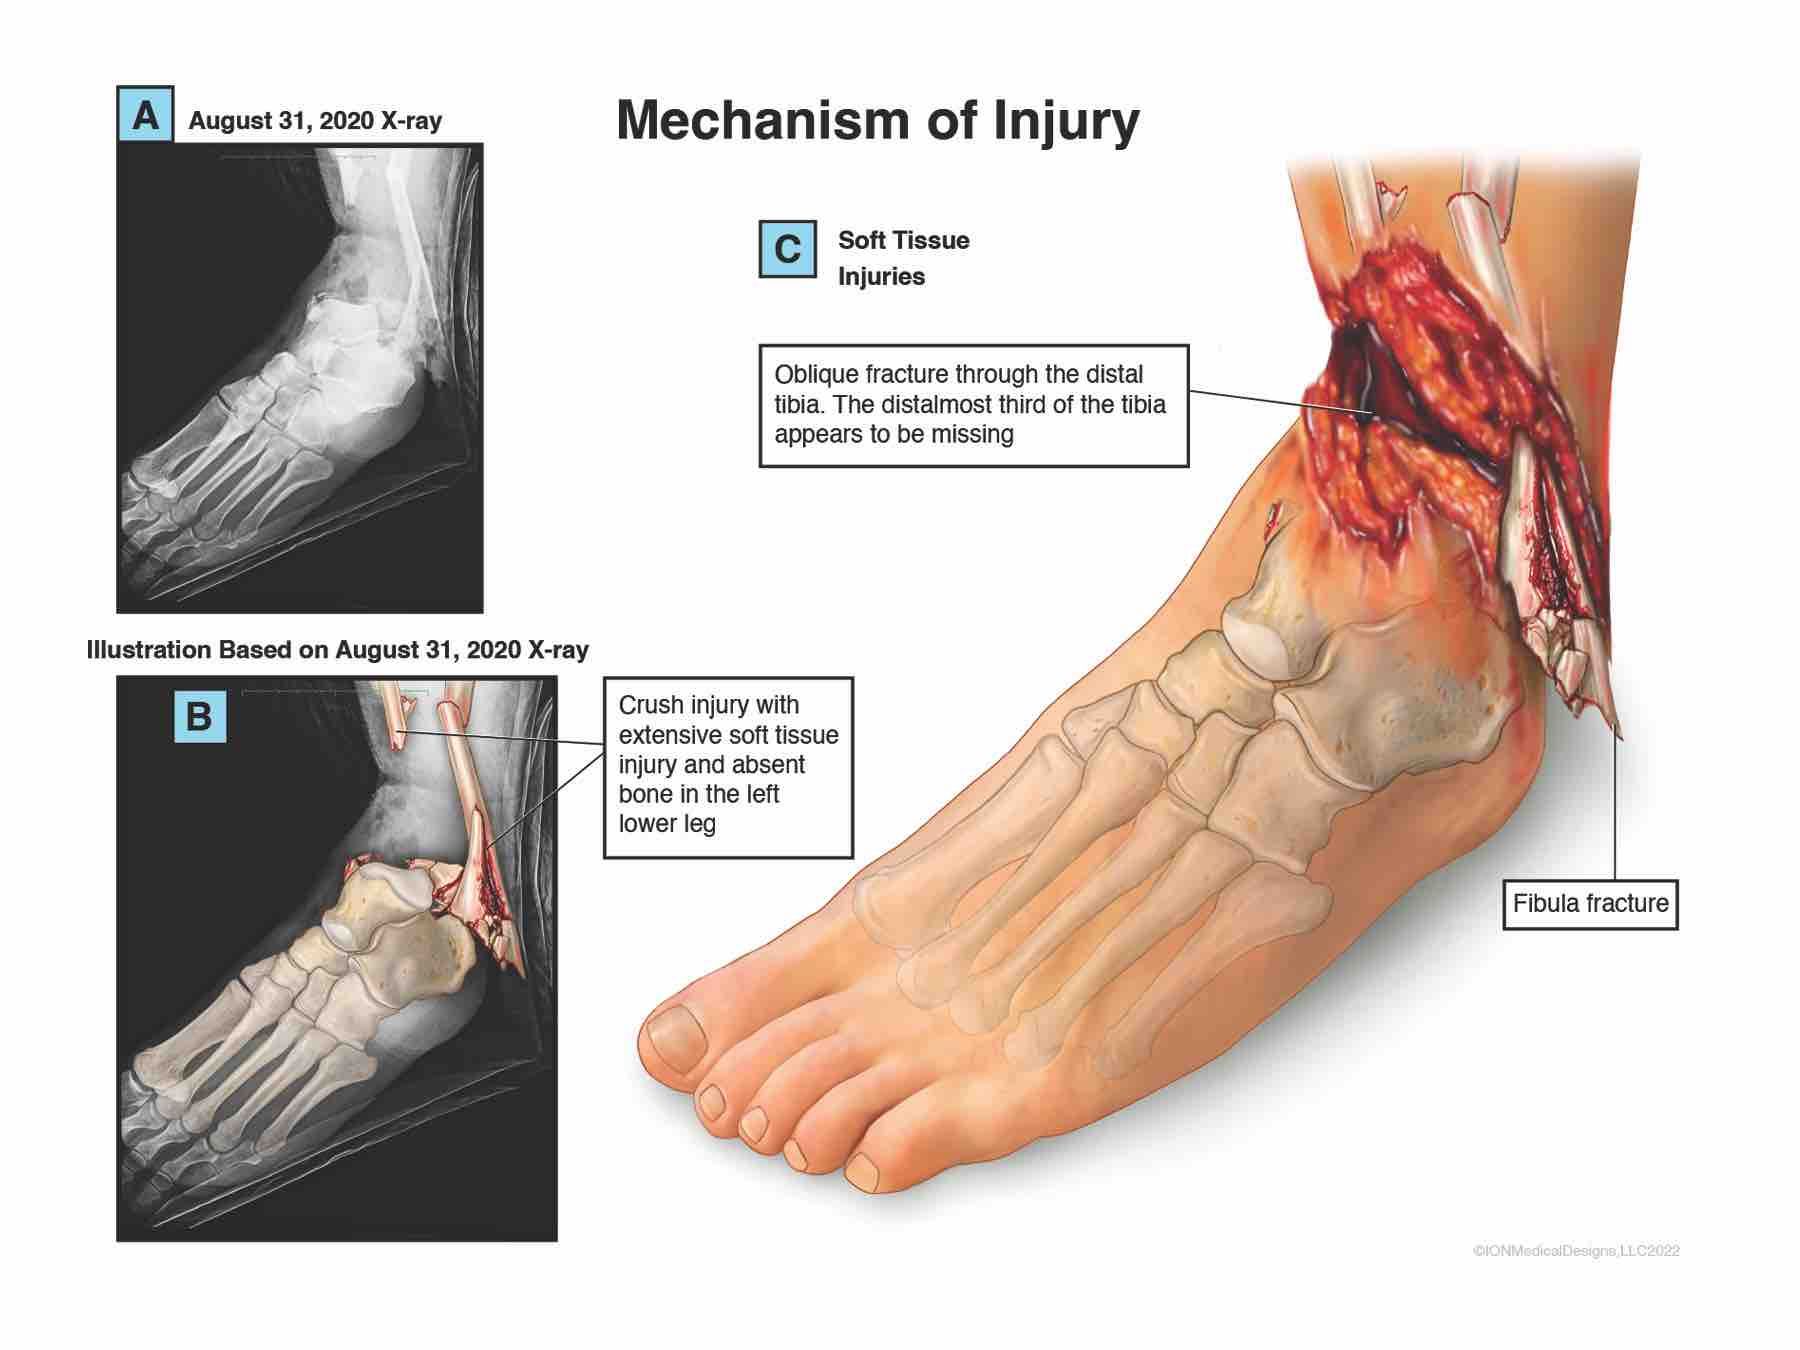

Cart Hit Woman's Ankle and Broke it

While working in the warehouse, the cart driver hit the woman's ankle and broke it.

Broken Ankle

Ankle After Forklift Hit

This illustration shows the victim's ankle after the forklift hit her.